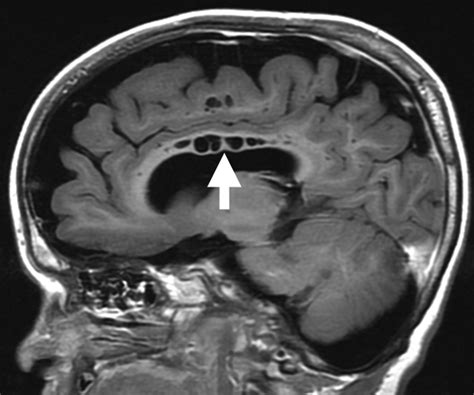

Due to its high concentration of neural pathways, the splenium of corpus callosum is a frequent area of interest in neuroradiology. Magnetic Resonance Imaging (MRI) is the gold standard for evaluating this region. Changes in the integrity of the splenium can be a marker for a variety of neurological conditions, ranging from developmental disorders to acute inflammatory processes.

When clinicians observe signal abnormalities in the splenium, they often look for what is termed "reversible splenial lesion syndrome" (RESLES). This condition often presents with acute onset of symptoms such as confusion, seizures, or vision changes, but interestingly, the lesions often resolve over time without permanent damage. This highlights the unique vulnerability and resiliency of the splenium to metabolic and inflammatory stressors.